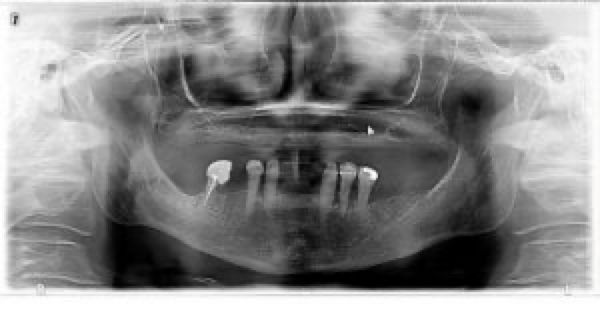

Parodontitis

Lückenzahnsystem mit generalisierter chronischer Parodontitis und Kippung der letzten Mahlzähne im Ober- und Unterkiefer rechts sowie Hinauswachsen der Frontzähne des Oberkiefers durch fehlende Gegenkieferbezahnung.